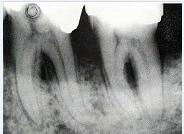

Ⅳ度根分叉区病变,最不需作哪项治疗()

A . 牙髓切除术

B . 牙周翻瓣手术

C . 洁治术

D . 刮治术

E . 根面平整术